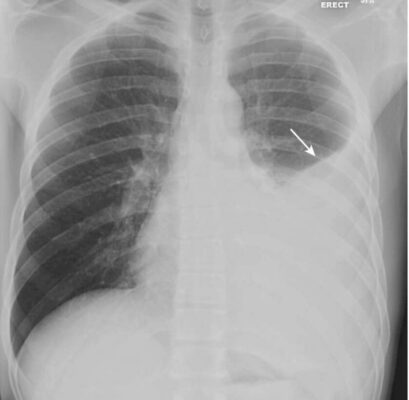

- Bệnh khoang chứa khí có đặc điểm là tạo ra các đám mờ ở phổi có thể được mô tả là như lông tơ, như đám mây hoặc mờ (fluffy, cloudlike, or hazy).

- Những đám mờ mịn như lông tơ này có xu hướng hợp lại, có nghĩa là chúng hòa trộn vào nhau với bờ không thể nhận thấy rõ.

- Các bờ viền của bệnh khoang chứa khí không phân biệt rõ, có nghĩa là thường khó xác định một điểm phân giới rõ ràng giữa bệnh và phổi bình thường lân cận.

- Bệnh khoang chứa khí có thể phân bố khắp phổi, như trong phù phổi (Hình 1), hoặc có thể khu trú hơn, như trong bệnh viêm phổi thùy hoặc phân thùy (Hình 2).